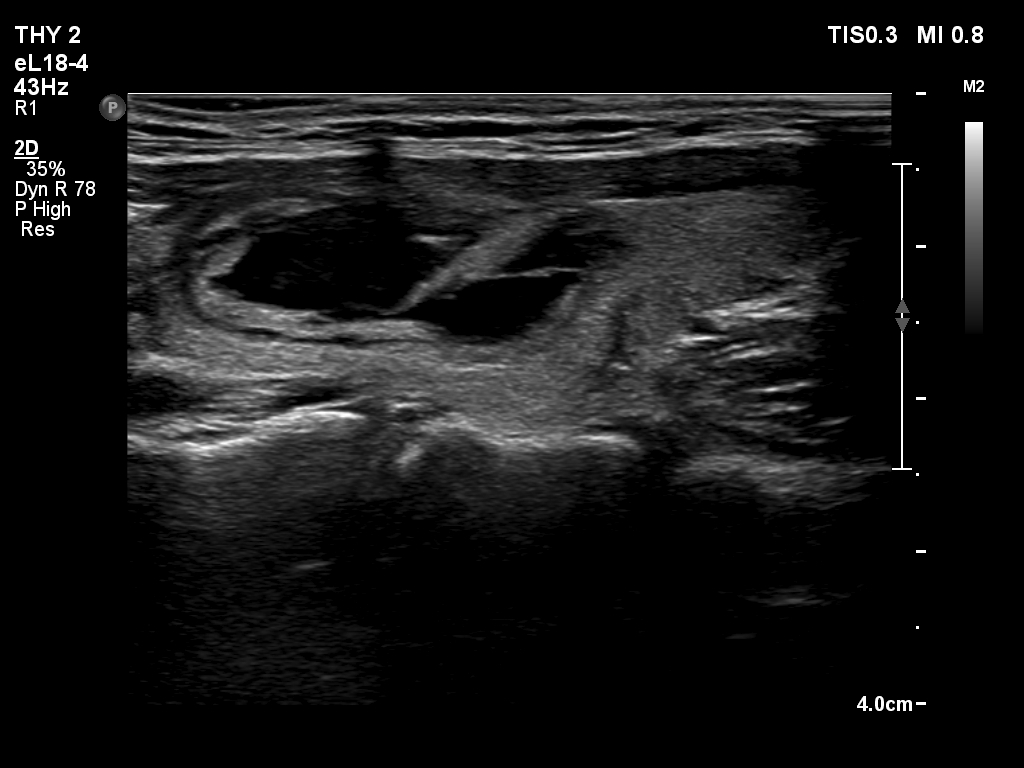

First session of sclerotherapy (third row of images):

Clinical presentation. Half a year has passed since the previous meeting. The patient noticed that the cyst has recurred 3 weeks ago.

Palpation: an elastic nodule in the left lobe.

Ultrasonography. The pattern was the same as what we saw at the first examination except for an increase in nodule volume.

16 mL brown fluid was aspirated, then 3.8 mL ethanol was injected. The therapy caused no complaints.